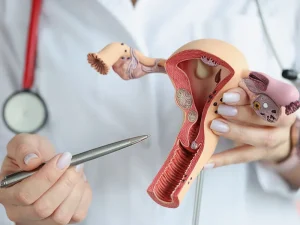

فیبروم و کیست تخمدان دو مشکل شایع در ناحیه زنان هستند که اغلب با یکدیگر اشتباه گرفته میشوند، اما از نظر ساختار، منشا و تاثیرات

فیبروم رحم در بارداری، یکی از موضوعات مهم و نگران کننده برای بسیاری از زنان در سنین باروری است. فیبرومها تودههای غیر سرطانی هستند که

فیبروم رحم یکی از شایعترین تودههای غیر سرطانی خوشخیم در میان زنان در سنین باروری است که در دیواره رحم یا اطراف آن رشد میکند.